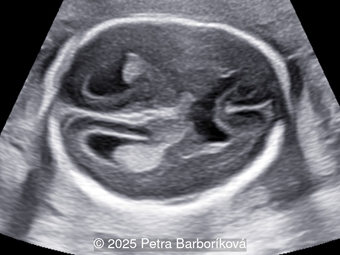

A 26-year-old primigravida with no significant past medical or family history was admitted at 18 weeks of gestation with preterm premature rupture of membranes. At 20 weeks of gestation, a detailed fetal ultrasound was performed under conditions of severe oligohydramnios, followed by fetal magnetic resonance imaging (MRI). Non-invasive prenatal testing (NIPT) for common aneuploidies was negative.